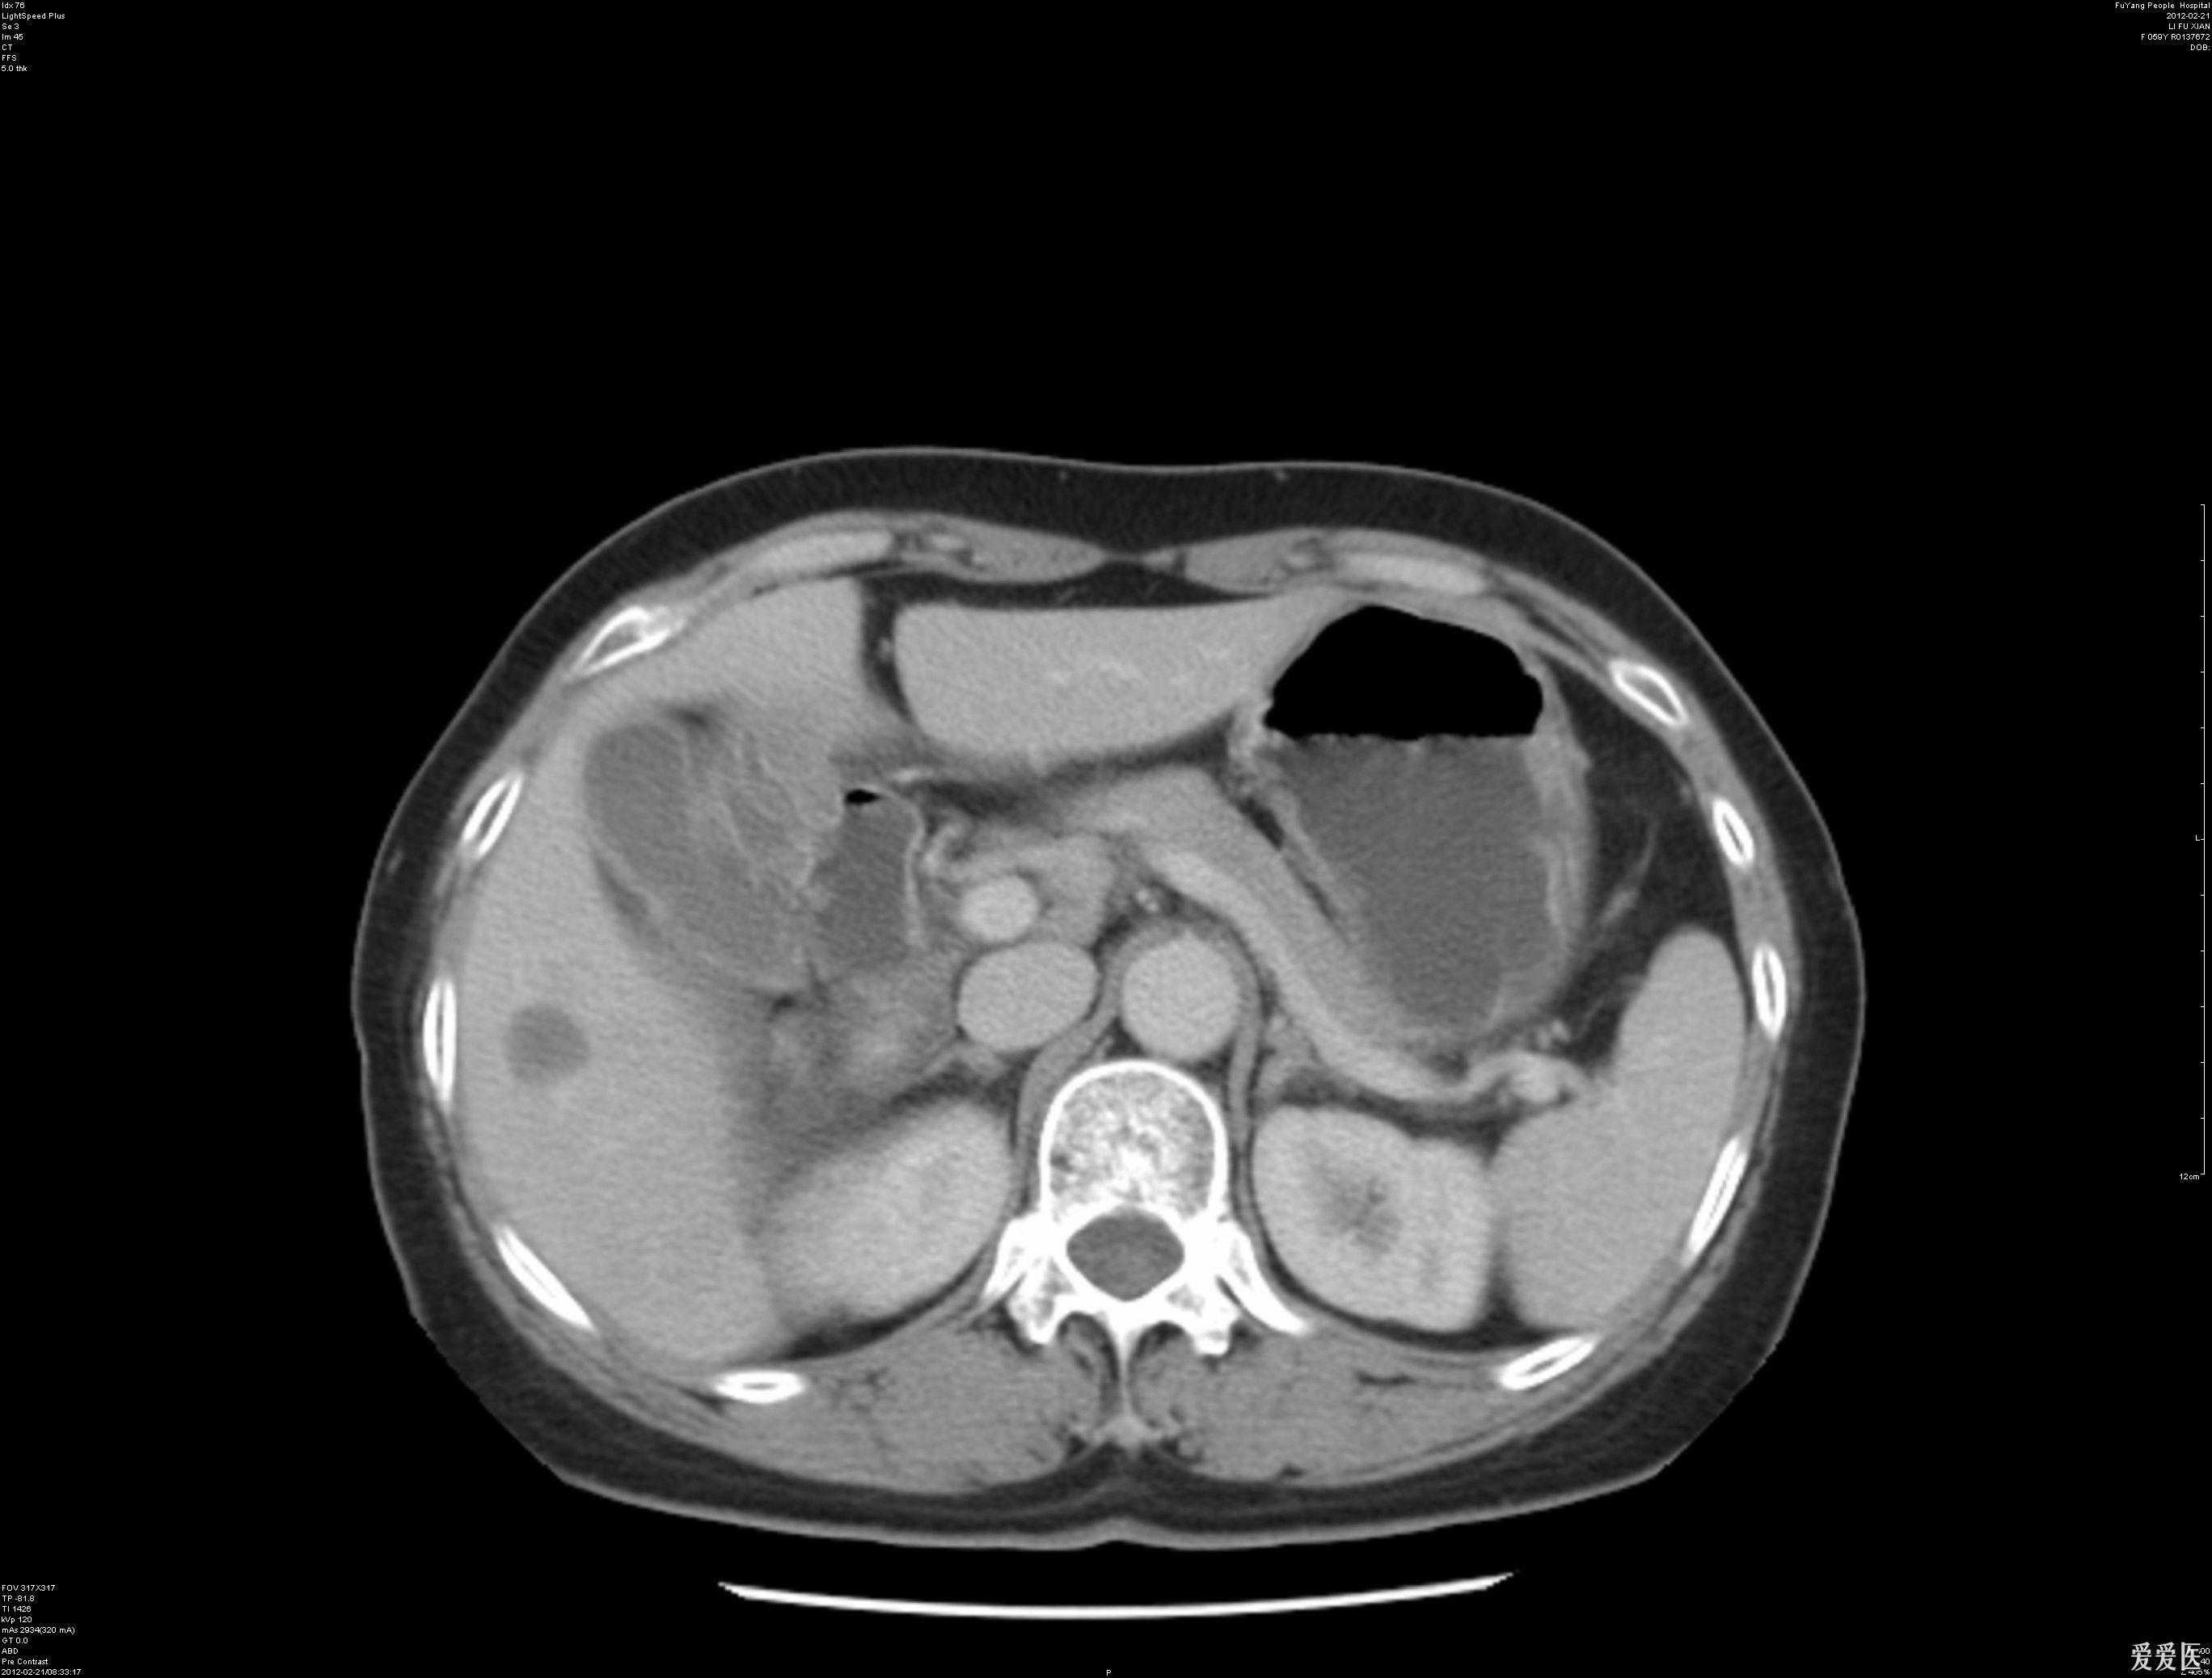

肝内占位影像检查